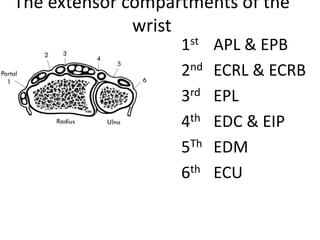

- It describes flexor tendon zones, extensor compartments, and pulley system anatomy.